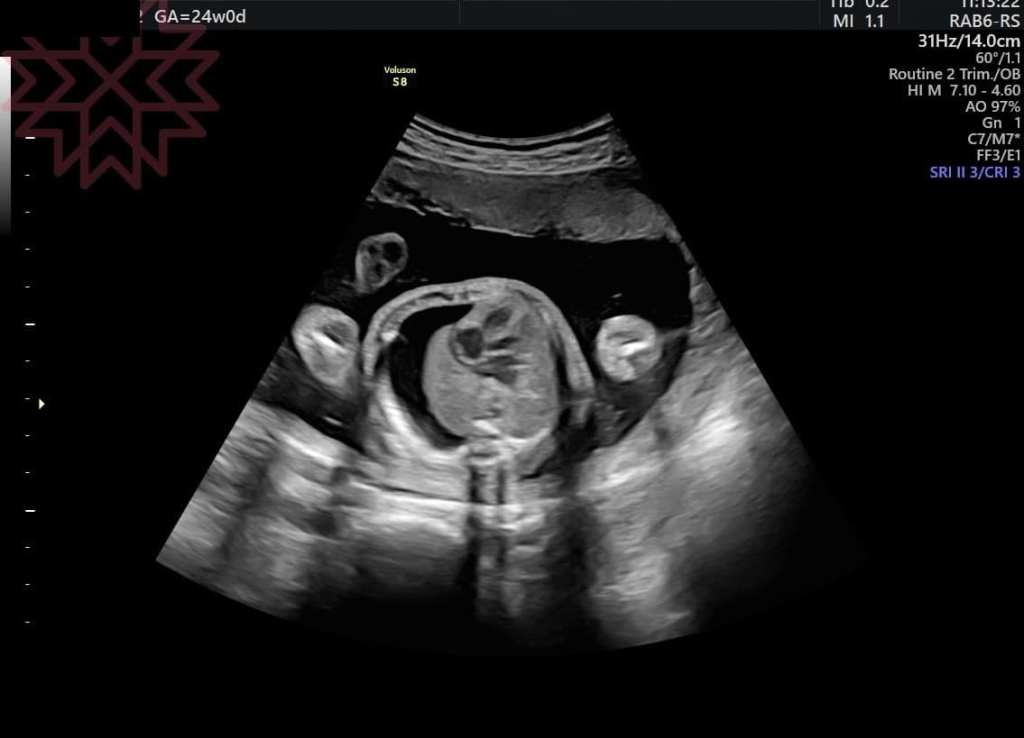

24週

單側乳糜胸

(如第一張影像

評估完超音波之後